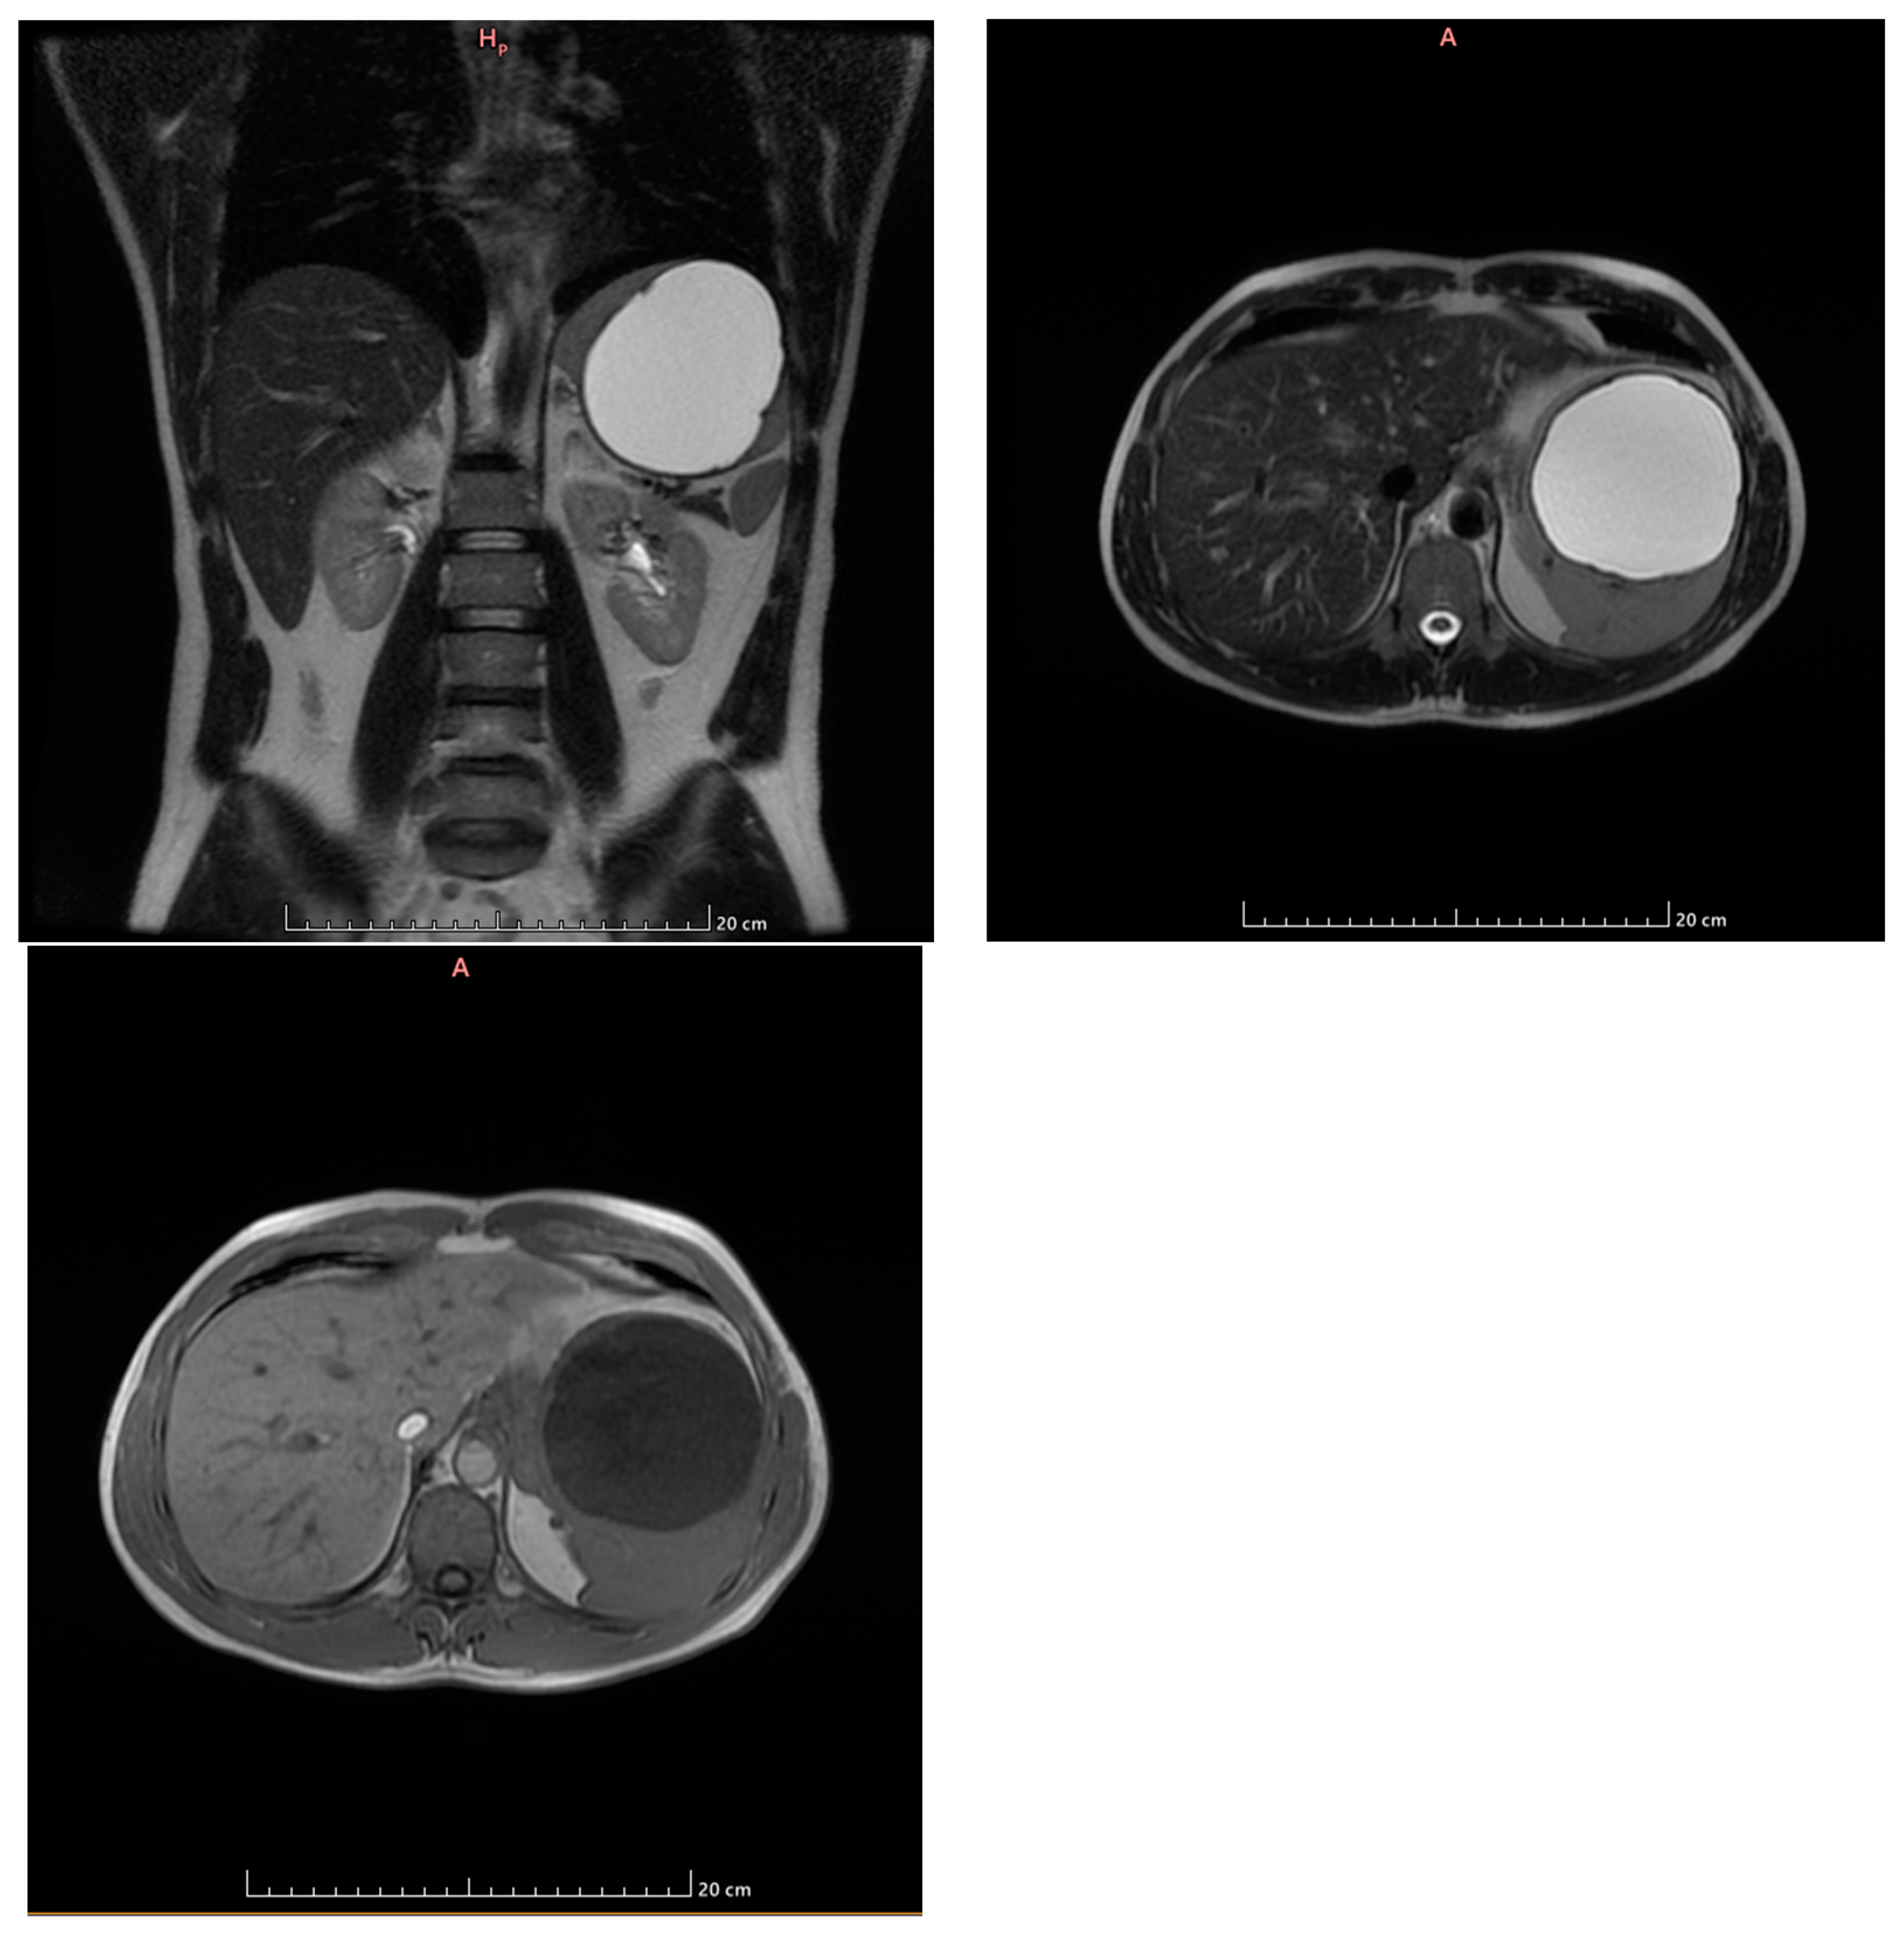

- Grade I splenomegaly with simple voluminous splenic cyst, 10 cm in diameter.

- Accessory spleen adjacent to the lower pole of the spleen.